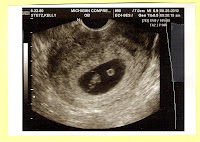

In baby news, Matt and I went to our second ultrasound today. So far the baby is healthy, growing and has a strong heartbeat! We are thrilled!

I have always wanted to start a blog, but never really had a good starting point for one. Now I guess we do....Katelyn is finally going to be a big sister! Baby #2 is on it's way and due April 5th. It has been a long journey and Matt and I are thrilled with the news. We are even more thrilled that we got to see the baby's

heartbeat at an ultrasound at 6 1/2 weeks.